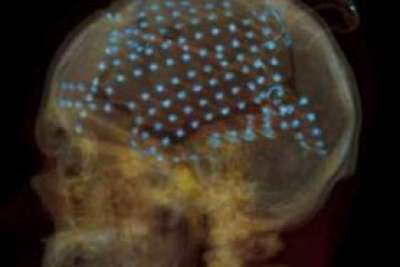

ابتكر العلماء برنامج كمبيوتر يستطيع أن يفك شفرة النشاط الدماغي وترجمة الأفكار إلى كلمات مقروئة، وتحديدا عند فاقدي النطق لأسباب مرضية.

وقال العلماء إن الابتكار الحديث يساعد فاقدي النطق -بسبب جلطة أو مرض ما- ليصبح لديهم خط تواصل مع الآخرين. وفي المقابل، تخوف آخرون من البرنامج الذي يستطيع الوصول إلى الأفكار وإعادة إنتاجها بطريقته الخاصة. وأجرى اختصاصيو أعصاب في جامعة كاليفورنيا بيركلي تجارب على بعض المرضى، عبر وضع أجهزة تحسس في الدماغ من أجل ترجمة الأفكار الواردة إلى صور أو كلمات.

ثم قام جهاز كمبيوتر مبرمج بتحليل نشاط الدماغ عند سماع المريض لأحاديث الآخرين ومراقبة كيفية إعادة استخدام الكلمات التي سمعوها.

ويعتقد العلماء أن بإمكانهم استخدام التقنية نفسها لعرفة ماذا يفكر المريض، وبالتالي ترجمة هذه الأفكار بشكل تقرير.

وذكر معدو الدراسة لدورية 'PLoS' البيولوجية أن الاكتشاف الحديث يأخذ عملية قراءة الأفكار إلى بعد جديد. ووافق مرضى مصابون بأورام دماغية على وضع 256 جهاز تحسس داخل أدمغتهم أثناء استماعهم لما يقوله المحيطون بهم، كي يدرس العلماء كيف أعاد الدماغ استخدام الكلمات التي سمعوها.

وتوقع العلماء أن يتم التوصل إلى جهاز تفاعلي يتم ربطه بالدماغ، يمكّن فاقدي النطق من تحويل أفكارهم المتواردة إلى كلمات مطبوعة.

وطمأن اختصاصي بريطاني المتخوفين من انتهاك حرمة أفكارهم، أن الجهاز يمكن تطبيقه فقط على المرضى الذين تعرضوا لجراحة تمكنهم من الربط بين دماغهم والجهاز المنشود، وأكد أن خصوصية الأفكار وسريتها آمنة من هجمات الهاكرز أو المتطفلين .